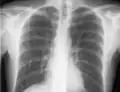

The line is then inserted using the Seldinger technique: a blunt guidewire is passed through the needle, then the needle is removed. A dilating device may be passed over the guidewire to expand the tract. Finally, the central line itself is then passed over the guidewire, which is then removed. All the lumens of the line are aspirated (to ensure that they are all positioned inside the vein) and flushed with either saline or heparin.[1] A chest X-ray may be performed afterwards to confirm that the line is positioned inside the superior vena cava and no pneumothorax was caused inadvertently. On anteroposterior X-rays, a catheter tip between 55 and 29 mm below the level of the carina is regarded as acceptable placement.[36] Electromagnetic tracking can be used to verify tip placement and provide guidance during insertion, obviating the need for the X-ray afterwards.

Chest x-ray with catheter in the right subclavian vein